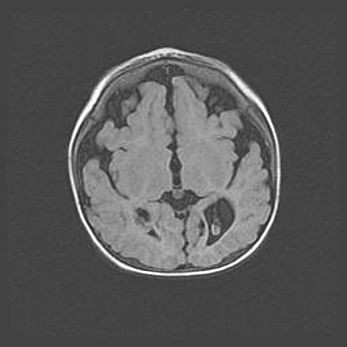

Сообщающаяся гидроцефалия. Кистозная энцефаломаляция головного мозга.

Возраст: 3 месяца 4 дня

Вес: 3100 г

Пол: женский

Окружность головы: 34 см

Срок гестации: 31 неделя

Кистозная энцефаломаляция головного мозга - одна из форм поражения головного мозга в детском возрасте. Характеризуется возникновением множественных и распространённых кист в коре, белом веществе и подкорковых образованиях головного мозга у плодов, новорождённых и детей раннего возраста. Развитие кистозной энцефаломаляции связано с внутриутробной асфиксией и гипотонией, родовой травмой, тромбозом синусов, пороками развития сосудов, инфекциями, сепсисом и другими причинами. Наиболее значимые инфекционные агенты: вирусы простого герпеса, цитомегалии, краснухи, токсоплазмы, энтеробактерии, золотистый стафилококк и другие.